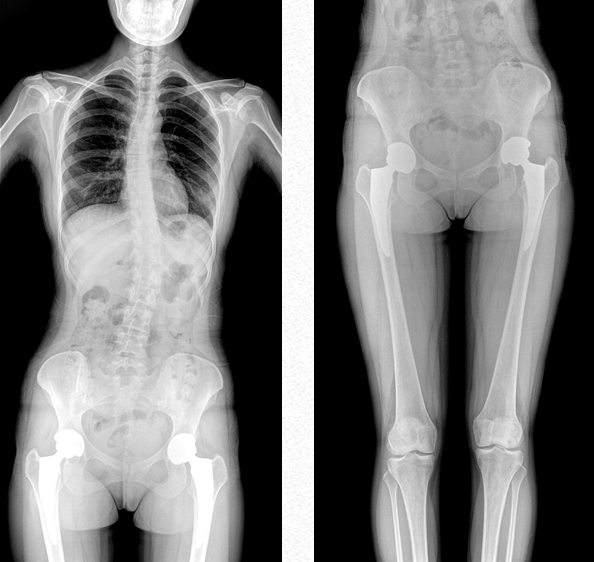

超大視野范圍,一次成像不拼接,減少拍片次數(shù),縮短拍攝時間,降低患者的輻射劑量吸收

全脊柱成像

用于全脊柱攝影,為臨床提供準確的二維影像,支持全脊柱斜位透視診斷,方便對椎弓根峽部進行觀察,診斷腰椎是否滑脫。如:先天性脊柱側彎、后凸畸形、多節(jié)脊柱創(chuàng)傷等。此外,大視野動態(tài)透視功能,在全脊柱脊髓造影的臨床應用中也頗具優(yōu)勢。

雙下肢成像

用于創(chuàng)傷弓|起的四肢骨折,進行較長髓內釘術前診斷、術后復診的大視野攝影。